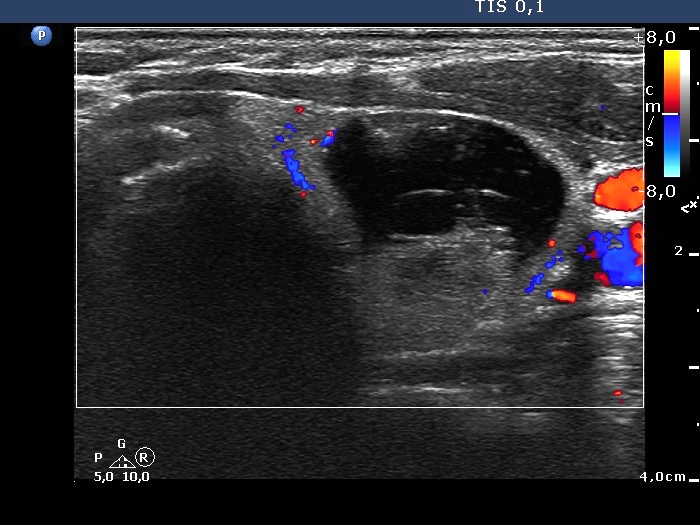

The composition of the nodule - case 142

Examination 3 years later (ultrasonographic picture 13)

Right lobe, longitudinal scan

Left lobe, another transverse scan, color Doppler mode.